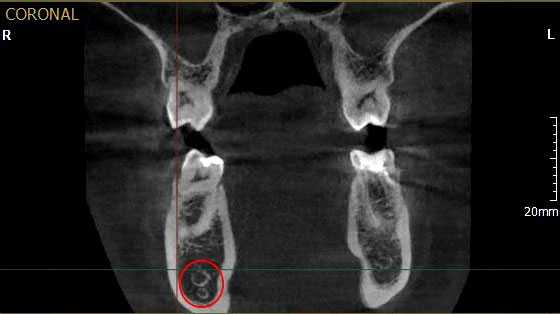

Рис. 1. Асимметричное строение нижнеальвеолярного нерва, добавочный канал в области нижней челюсти справа во фронтальной проекции конусно-лучевой компьютерной томографии от Vatech.

Первая - легкая степень обусловливалась сдавлением ствола за счет отека, гематомы или прямой, непосредственной, но незначительной компрессией имплантатом. Рентгенологическое исследование посредством конусно-лучевой компьютерной томографии и программного обеспечения Ez3D-iV4.3.0 от Vatech, при маркировке нижнечелюстного канала, установило расположение дентальных имплантатов непосредственно у нижнечелюстного канала или эндопротезы перфорировали верхнюю стенку канала (Рис.2). Тактика лечения такого вида патологии основывается на сохранении имплантатов, назначении витаминов группы В, средств, оказывающих непосредственное стимулирующее влияние на проведение импульса по нервным волокнам, усиливающих сократимость гладкомышечной мускулатуры под влиянием агонистов ацетилхолиновых, адреналиновых, серотониновых, гистаминовых и окситоциновых рецепторов. Нарушение чувствительности во всех наблюдениях этой группы носило временный характер и восстановилось через 4–6 недель.

Рис.2 Конусно-лучевая компьютерная томография от Vatech. Нижнечелюстной канал маркирован с помощью программного обеспечения Ez3D-iV4.3.0.

Результаты рентгенологического исследования показали, что дентальная объемная томография наиболее информативный метод при оценке степени повреждения нижнего альвеолярного нерва. Истинное трехмерное изображение исследуемого объекта и вращение его вокруг любой из трех осей на 360 градусов, позволяют визуализировались положение имплантата по отношению к нижнечелюстному каналу и документировать степень его повреждения. Программное обеспечение Ez3D-iV4.3.0 от Vatech предполагает огромный функциональный набор. Применительно к диагностике повреждения нерва после имплантации в данном софте в режиме высокого качества разрешения возможна трехпроекционная реконструкция, с возможностями переориентации осей, с измерением габаритов объекта исследования в масштабе 1:1(рис.3).

Рис.3 Конусно-лучевая компьютерная томография от Vatech. На коронарной проекции определяется верхушка дентального имплантата 3.6, перфорирующая медиальную стенку нижнечелюстного канала.